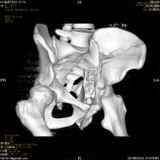

Уважаемые коллеги! Хотелось бы услышать совет по тактике лечения представлленого больного.Поступил после лечения в одном изотделений области. Травма 2,5 месяца назад. После выведенияиз шока был произведен остеосинтез перелома бедра, предплечья, до перевода к нам проводилосьвытяжение по оси шейки бедра за стержень, введенный в большой вертел. На сегодня деформацияригидна, клинически мобильности не определяется. Заранее признателен. P.S. Данный вид травм не включен в перечень "высокотехнологичных операций", направить длялечения по квотам Минздрава очень сложно.

Это обзорные и косые снимки

С уважением,

Leonid

Привет, Леонид. Оскольчатый высокий двухколонный перелом в такие сроки трогать не надо, т.к. это про такие переломы сказано: "кто с ножом на Ж. пойдет тот в ней и останется...".